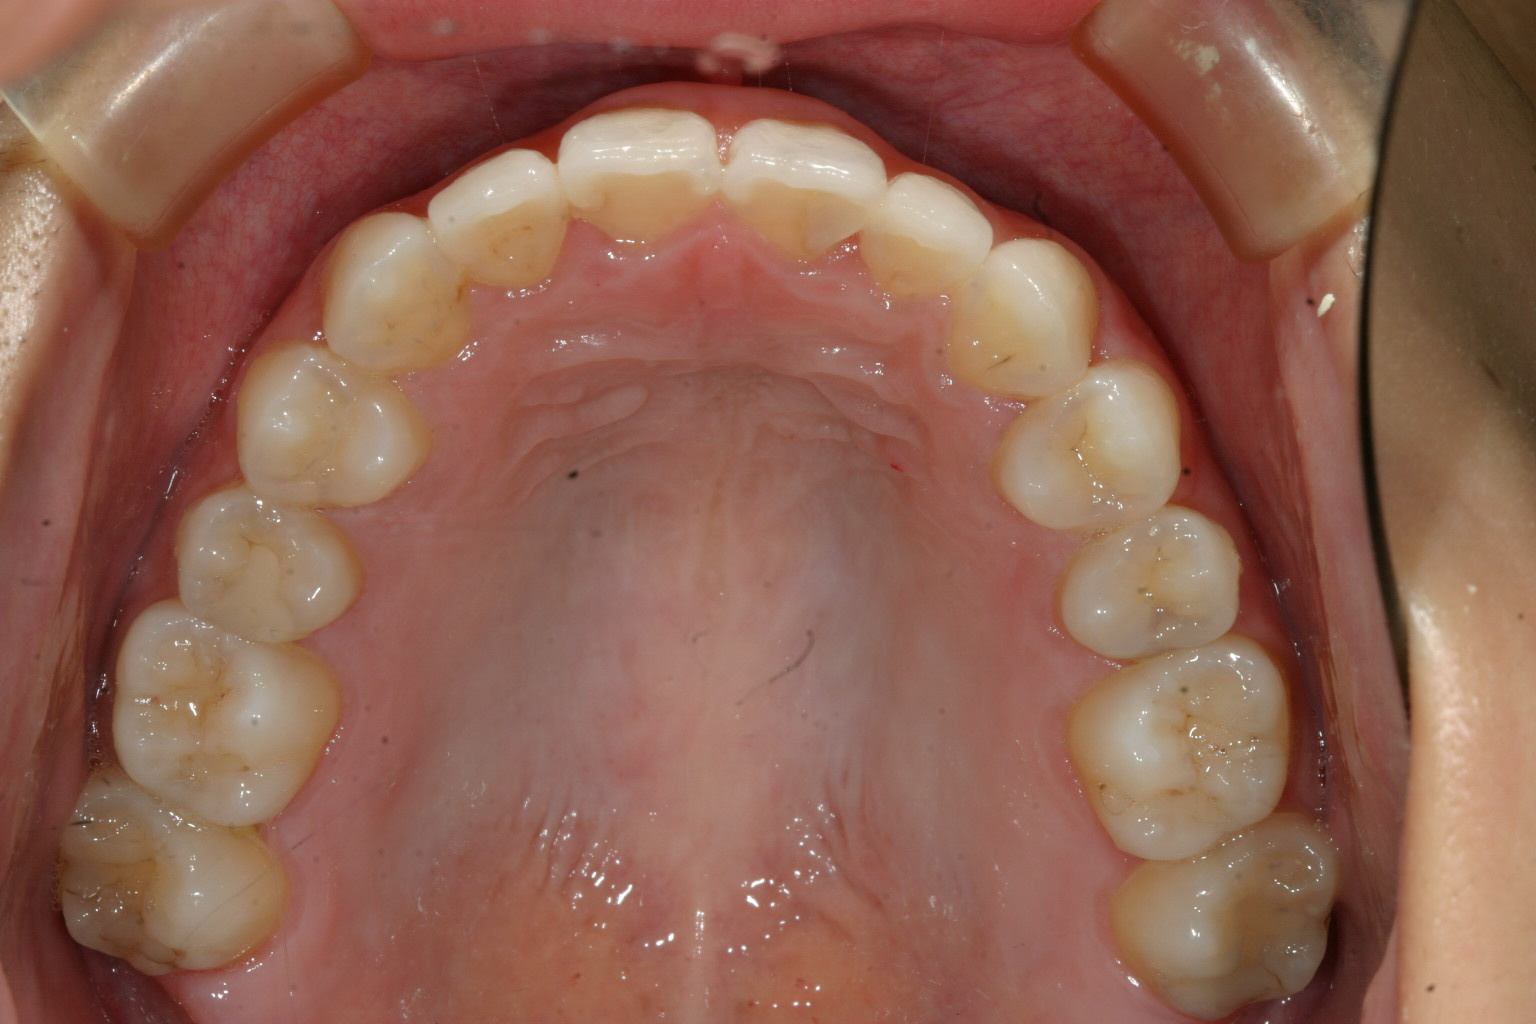

アーチを広げ綺麗に改善しました。

今回のインビザラインケースは小臼歯1歯抜歯する事で受け口の改善を試みました。

思ったより歯の動きが悪く少し時間を要しましたが結果的には綺麗に改善出来て私も

満足しています。

私としましては出来るだけ抜歯せずに治療したい派なんですが必要最小限の1歯で何とか

治療出来て良かったと思っています。